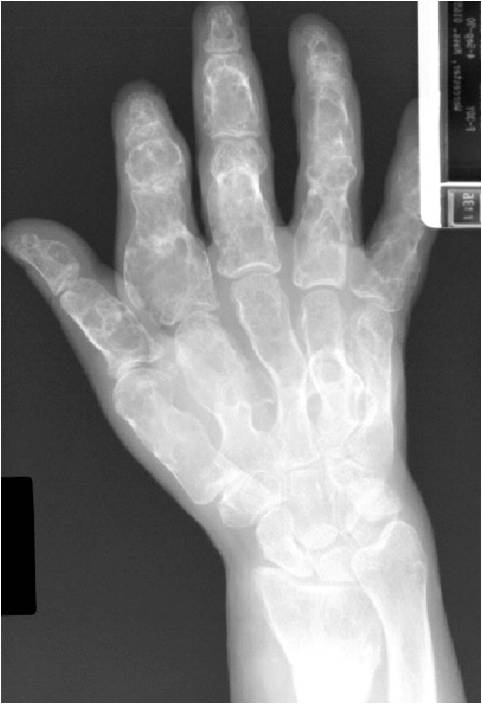

Geographic Lesion Bony Expansion Minimal Calcification Some Enchondromas do not calcify

Geographic lesion, Stippled calcifications in lesion, Phalanx is expanded, Significant endosteal scalloping, No cortical destruction, No soft tissue extension, Cortex Scalloped and Expanded